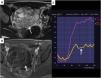

También pueden tener curvas de bajo riesgo los tumores borderline, aunque la morfología característica de su parte sólida nos permite realizar el diagnóstico de sospecha correctamente. Recomendamos familiarizarse con los hallazgos típicos de los tumores borderline leyendo los artículos referenciados a continuación14,15 (fig. 6).

Tumor borderline con curva de bajo riesgo. A) T1FS poscontraste. B) T2 sagital. C) Curva de bajo riesgo (flecha). En las imágenes podemos ver masas ováricas bilaterales con mínima captación de contraste que presentan una morfología arborescente y con crecimientos murales papilares (flechas) típicas de los tumores borderline. Recordemos que se prefiere operar los tumores borderline en centros oncológicos por su incierto potencial maligno.

Por último, hay que tener en cuenta que algunos tumores mucinosos borderline o malignos prácticamente no presentan tejido sólido y pueden clasificarse incorrectamente como lesiones Score 3. La morfología de las lesiones mucinosas también es muy típica y siempre que se sospeche deben descartarse tumores mucinosos de otro origen (colon, apéndice, etc.)10. Por otra parte, no es infrecuente que los tumores mucinosos, incluso los benignos, presenten pequeñas roturas y líquido mucinoso a su alrededor, que debe diferenciarse de la presencia de carcinomatosis peritoneal. En general, ante la sospecha de tumor mucinoso, con imagen característica, habrá que alertar al ginecólogo de dicha posibilidad (fig. 7).

Metástasis de tumor mucinoso apendicular. A) La imagen T2 es muy típica de los tumores mucinosos, son masas quísticas multiseptadas y sin prácticamente componente sólido (flecha). B) La imagen T1FS poscontraste muestra únicamente captación lisa mural de los septos. Ante tumores de estas características debe alertarse al oncólogo que podemos estar delante de una lesión mucinosa maligna primaria o metastásica.

Si la masa presenta una curva de contraste de riesgo intermedio en su componente sólido, será clasificada como O-RADS RM Score 4 (fig. 8) y si tiene una curva de contraste de alto riesgo, será clasificada como O-RADS RM Score 5 (fig. 9). En ambos casos la masa ovárica debe ser intervenida en un centro oncológico.

Metástasis ováricas bilaterales, primario intestinal. A) T2 axial. B) b1000. C) T1FS poscontraste. D) Curva de captación tipo 3 (flecha). Cuando veamos lesiones sólidas bilaterales, que restringen en difusión y muestran curva de captación de alto riesgo, aunque sean hipointensas en T1 debe sospecharse malignidad (flechas).